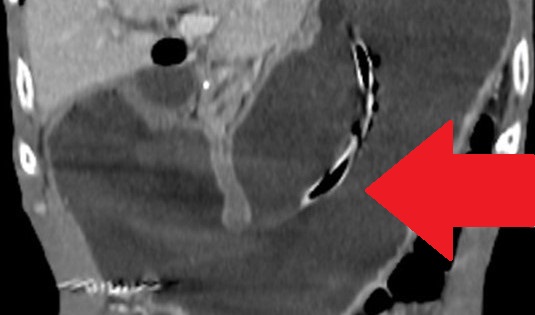

Diaphragmatic hernia before and after reduction of the stomach (Courtesy Dr. V. Penopoulos)